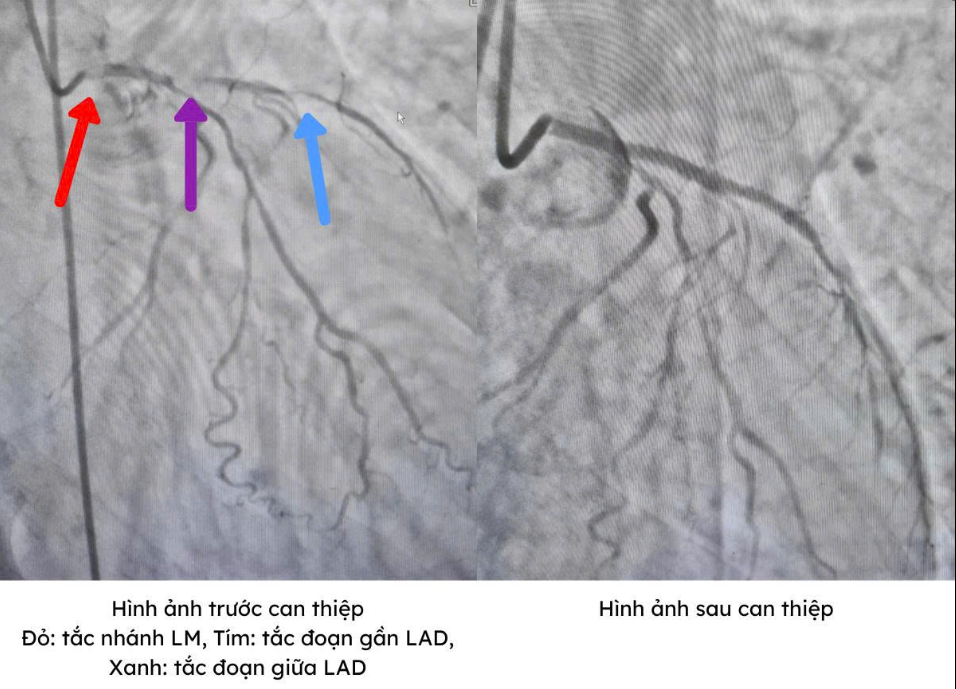

Kết quả chụp cho thấy: tim vốn được nuôi bởi 3 mạch máu chính, thì ở trường hợp này, hai mạch máu quan trọng nhất gần như tắc hoàn toàn, chỉ còn khoảng 5% khẩu kính, mạch máu thứ ba cũng bị bóp nghẹt đến 90%, còn nhánh mạch máu còn lại tuy hẹp ít hơn nhưng dòng máu đã giảm rõ rệt.

ngung-tim.png

Đây là dạng tổn thương đặc biệt nguy hiểm vì cả ba nhánh mạch vành chính đều bị hẹp nặng, khiến tim gần như không còn đủ máu để hoạt động. Bệnh nhân có thể ngừng tim bất cứ lúc nào, với tỷ lệ tử vong ước tính gần 90% nếu không tái thông mạch kịp thời.